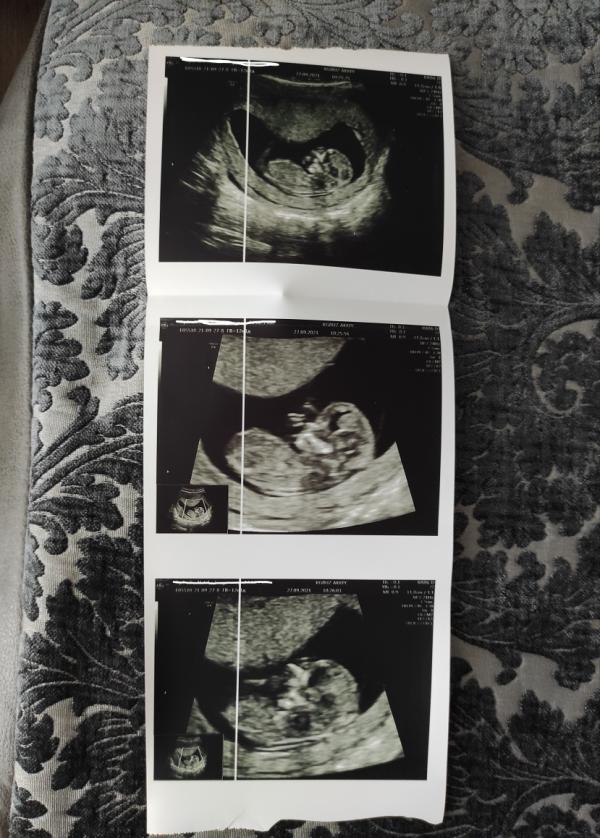

✅12 недель 1 день

✅1 скрининг пройден

По УЗИ врач сказала, что все хорошо. Вес 65 гр +- 9 гр 🤔 не много ли это? Все приложения пишут другой вес на этом сроке 🤷♀️ Но да ладно, все впереди. Самое главное, все размеры соответствуют сроку 👍

Единственное, меня смущает в заключении "неполное предлежание хориона". На прием к гинекологу в следующий понедельник, спрошу, что это и как.